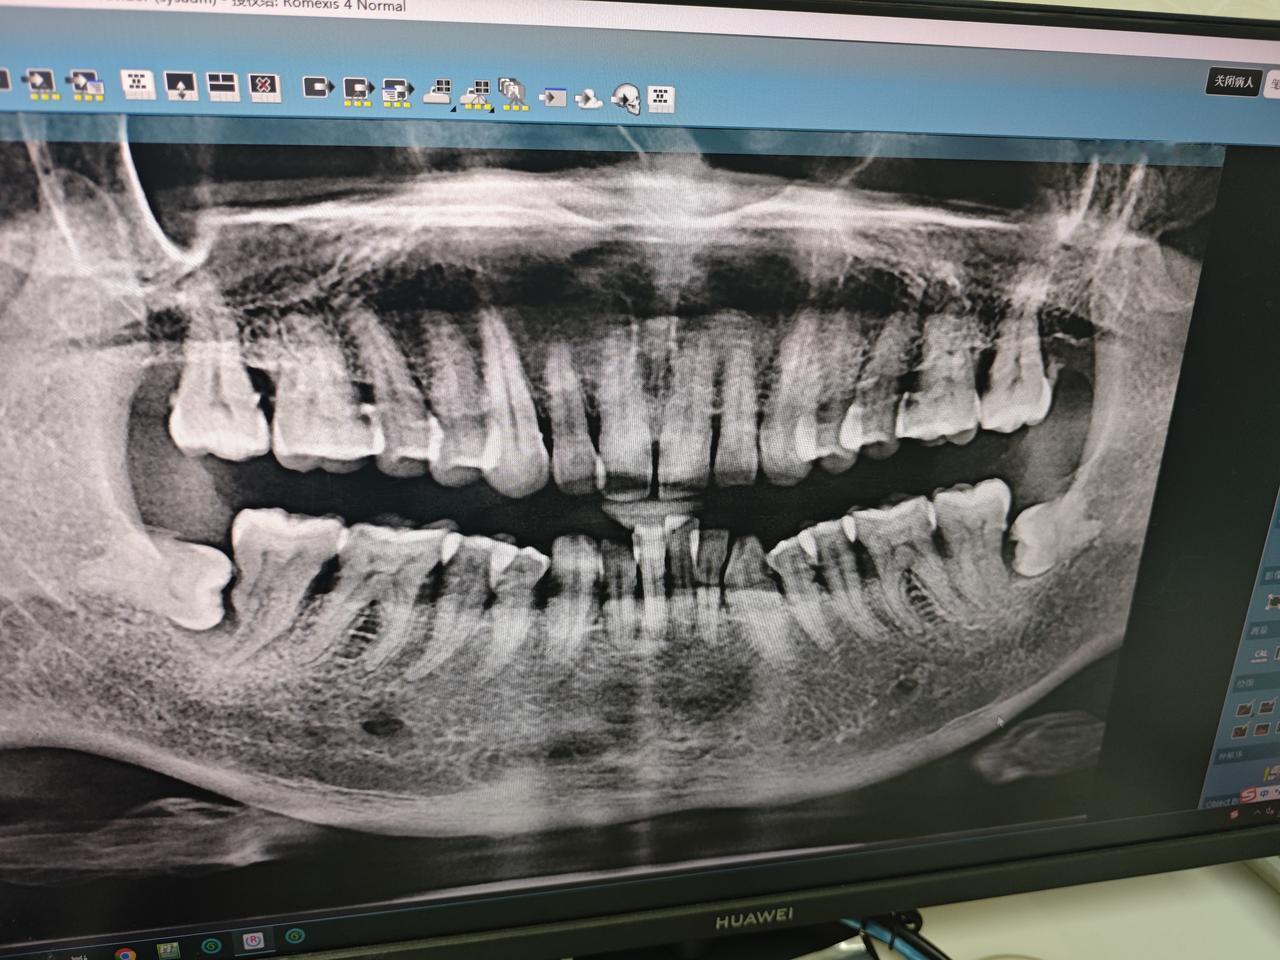

但愿早日普及,刚拔了一颗7号大磨牙吃饭都嚼不碎面条了